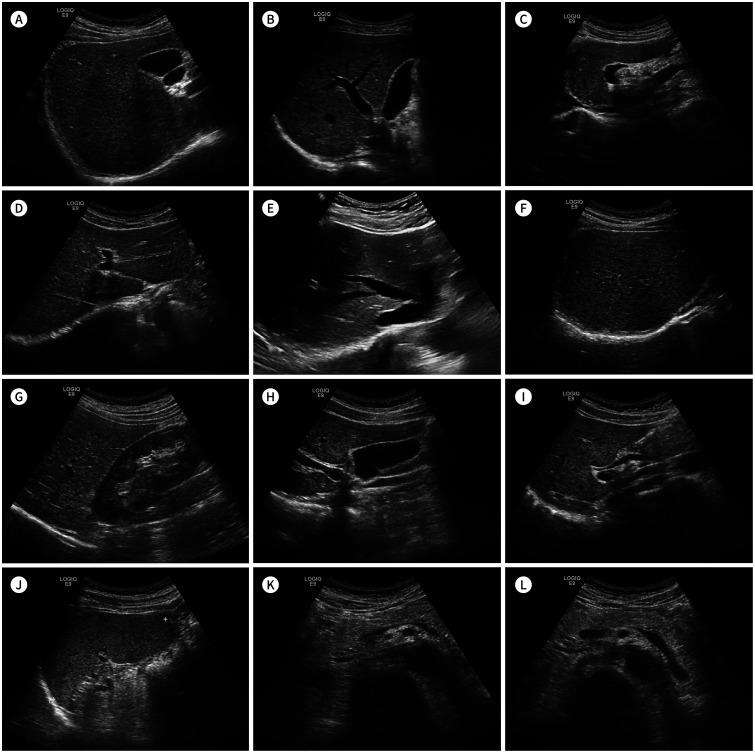

Coverage by National Health Insurance (NHI) was expanded in the abdominal imaging area as follows: upper abdominal ultrasound on April 1, 2018, lower abdominal ultrasound on February 1, 2019, and abdominal MRI on November 1, 2019. Many patients can benefit from the expansion of NHI coverage. Newly included diseases for NHI coverage includes liver cirrhosis, gallbladder polyps, hepatic adenoma/dysplastic nodules, pancreatic cysts, autoimmune pancreatitis and bile duct stone disease. However, the expansion of coverage made each examination more complex, including indications, follow-up strategy, the number of examination per patients, the standard images to be acquired, and the standard forms of the radiological report. Therefore, more careful consideration is mandatory when an abdominal imaging examination is prescribed and conducted.

国民健康保险(NHI)在腹部成像领域的覆盖范围扩大如下:2018年4月1日起覆盖上腹部超声,2019年2月1日起覆盖下腹部超声,2019年11月1日起覆盖腹部MRI。许多患者可从NHI覆盖范围的扩大中受益。NHI新纳入的覆盖疾病包括肝硬化、胆囊息肉、肝腺瘤/发育异常结节、胰腺囊肿、自身免疫性胰腺炎和胆管结石病。然而,覆盖范围的扩大使每次检查变得更加复杂,包括适应症、随访策略、每位患者的检查次数、要获取的标准图像以及放射学报告的标准格式。因此,在开具和进行腹部成像检查时必须更加谨慎地考虑。